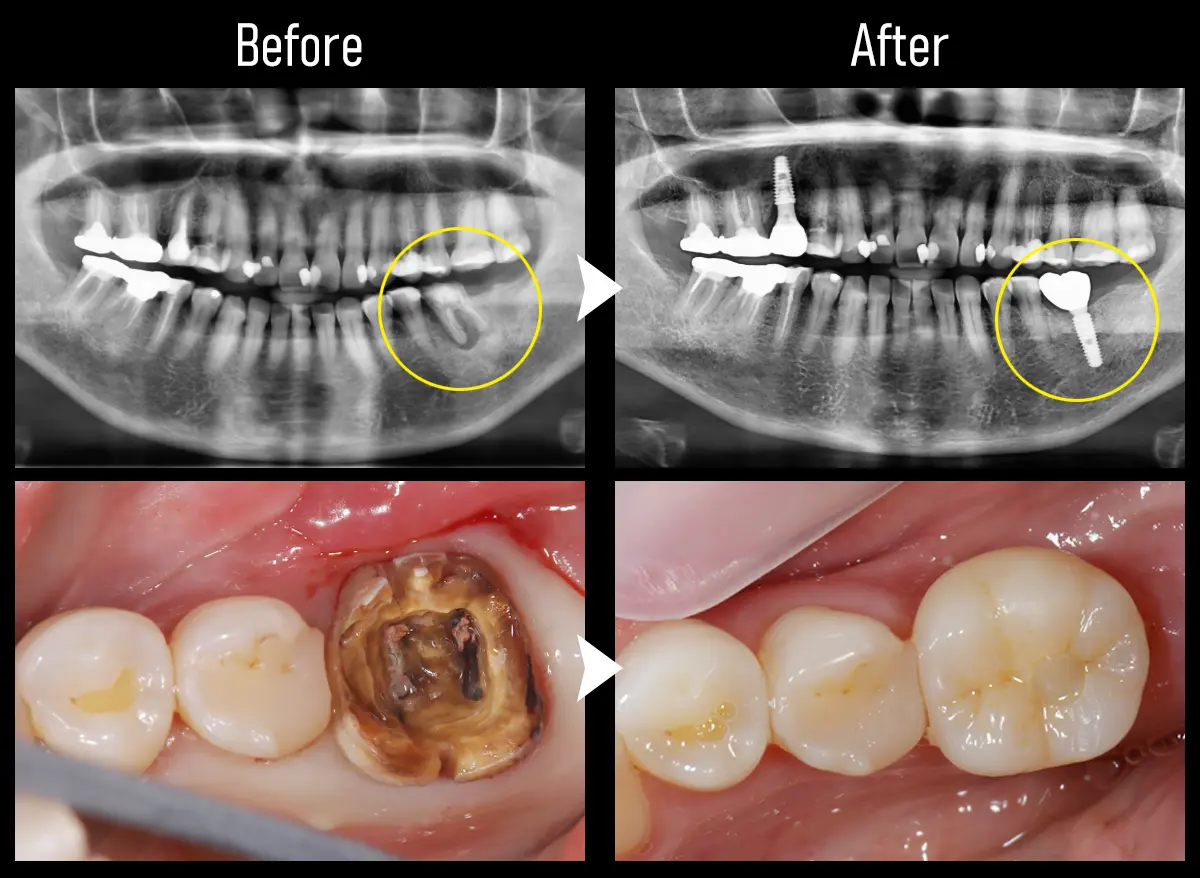

CASE:大臼歯1本

主訴 被せ物が取れた

治療内容 下顎左6番にインプラント治療

標準費用(自費) 55万円